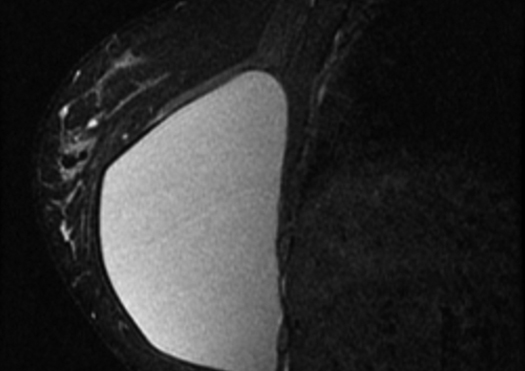

Mastografía

Técnica de rayos X para la obtención de imágenes de la glándula mamaria en distintas proyecciones, para la detección precoz de cáncer de mama en pacientes asintomáticas, que se realiza con tamizaje y periodicidad anual en la mayoría de los casos.